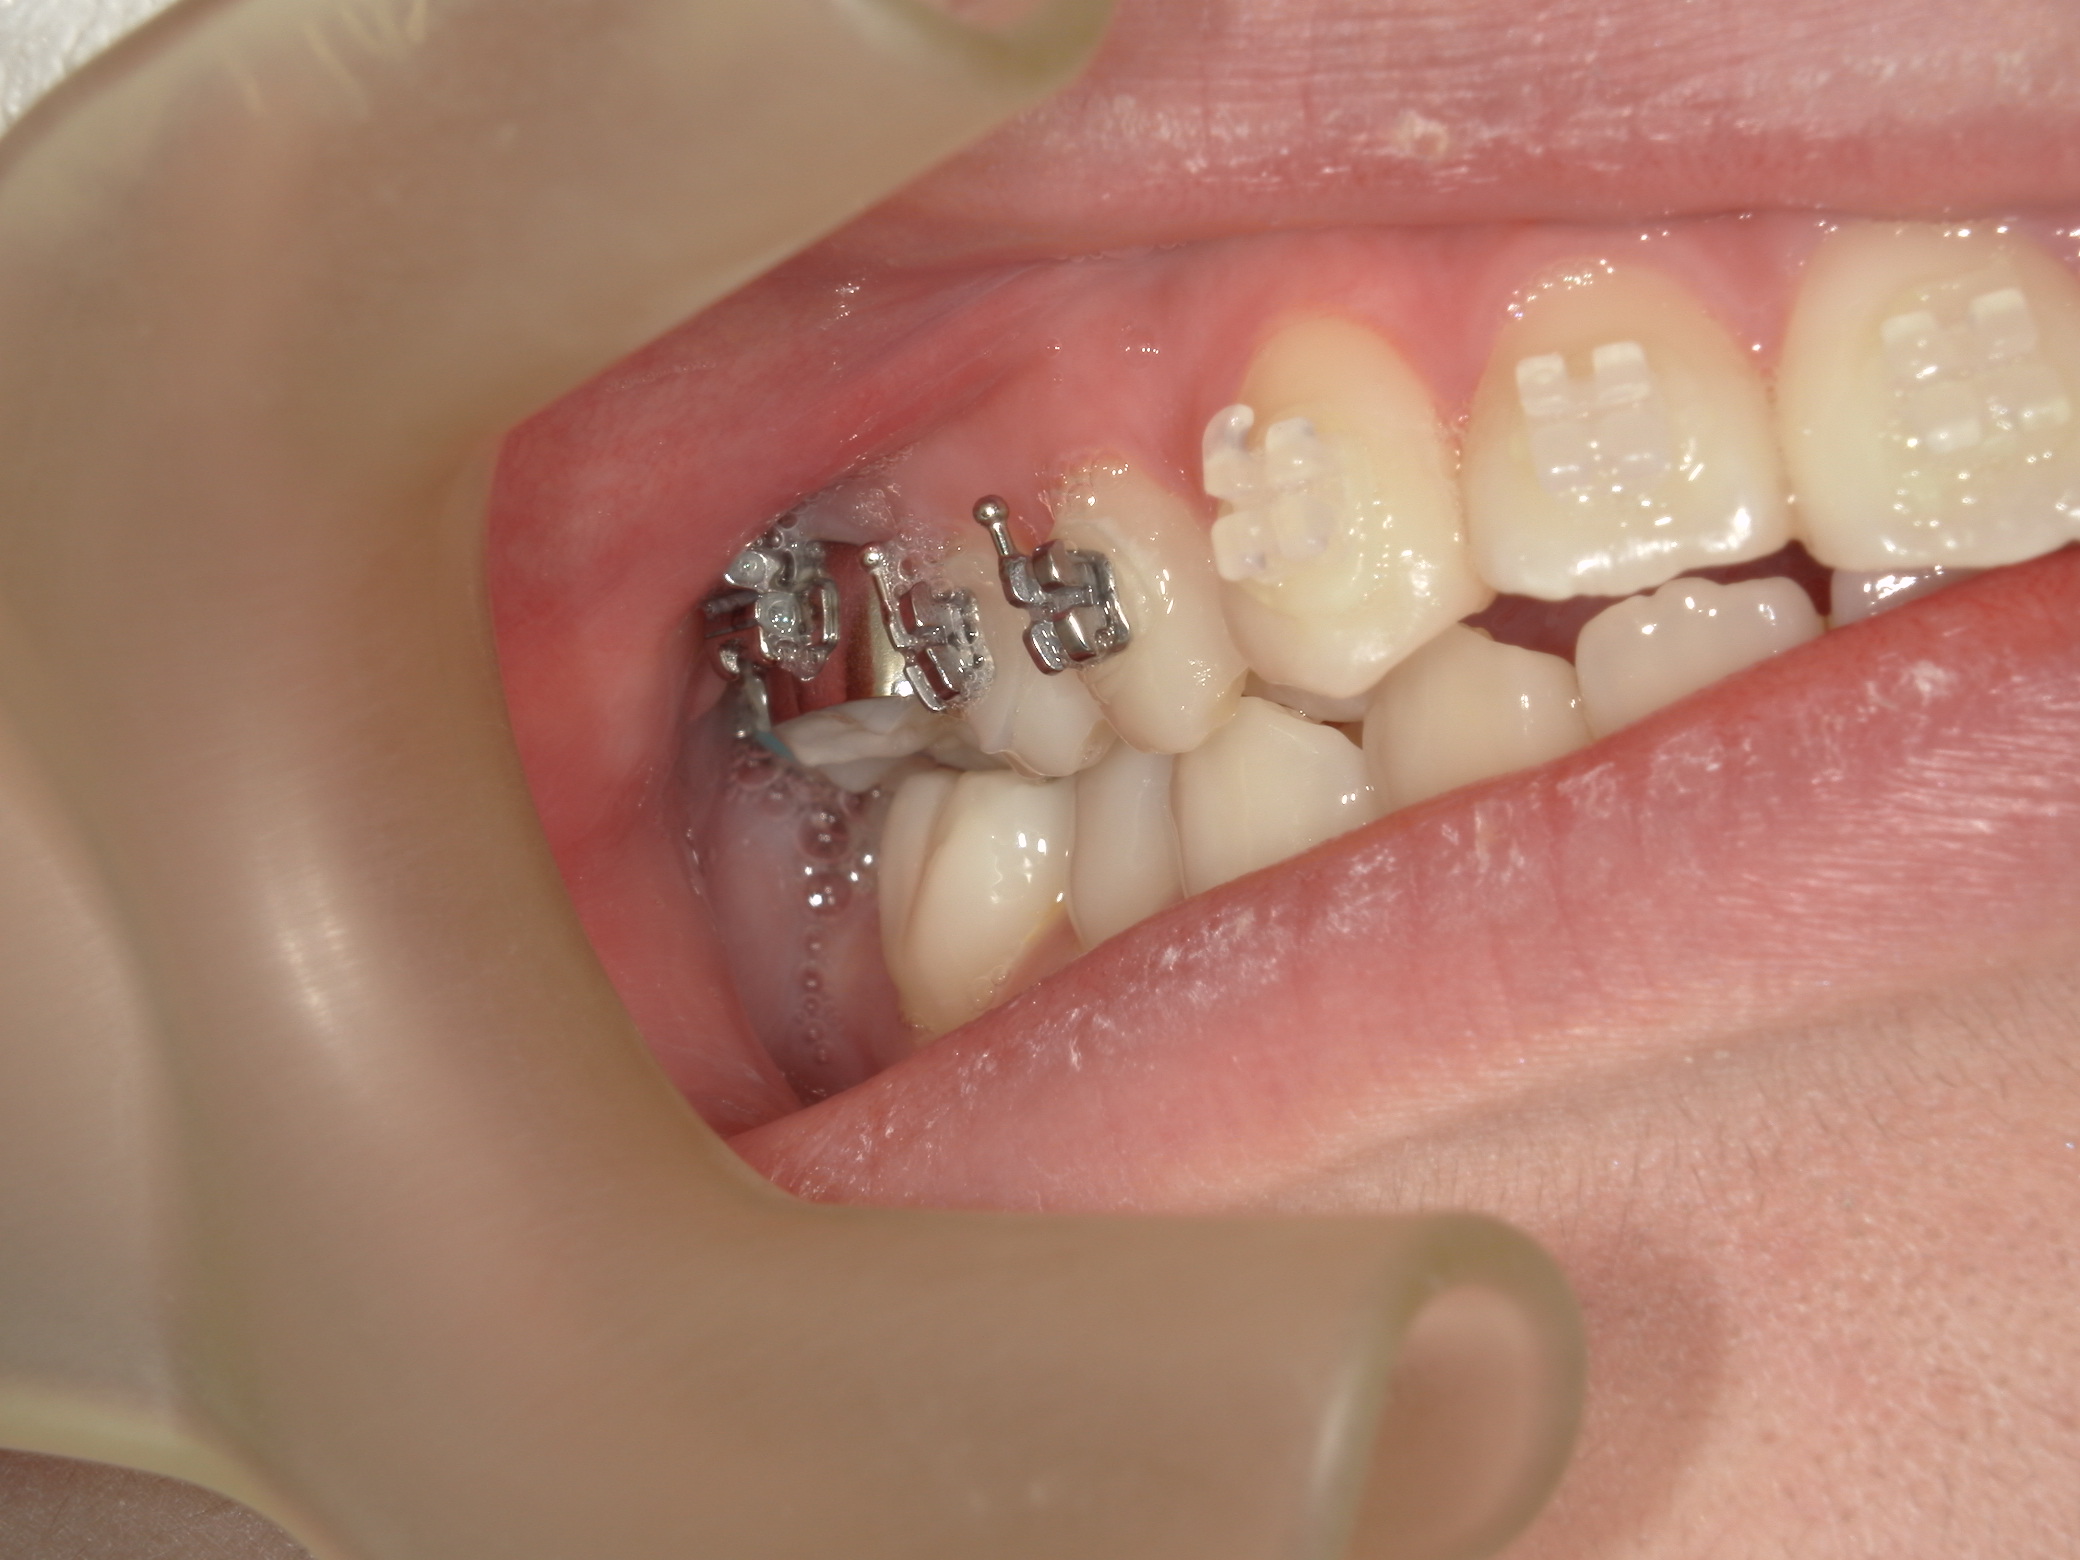

この症例の気になるの点として、無理な拡大で下顎左右6番の歯根が頬側の皮質骨からはみ出ている危険があることです。そうならば、下顎6番の近心移動はものすごく遅くなります。等と考えていたので、当然のごとく抜歯部位の選定に悩みました。悩んだ末、この症例は上下左右の6番抜歯症例です。